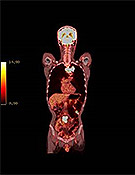

PETからPET-CTへ

当院では、PET検査と同時にCT検査が行える最新鋭機器『PET-CT』を導入しました。これにより、検査時間の短縮はもちろんのこと、PETによる細胞の機能診断画像とCTによる形態診断画像を重ね合わせることで、診断精度が大幅にアップします。

| <PET/CT Fusion画像> | <PET/CT Fusion画像> | <PET画像> | <MIP画像> |